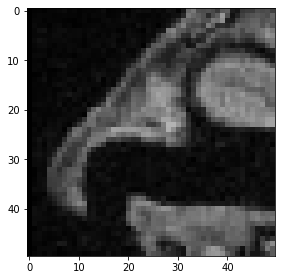

Por último, pero no menos importante, así es como se especifica un cubo recortado.

cropped_cube = image[80:130, 120:170, :50]

cropped_cube.shape

(50, 50, 50)

imshow(cropped_cube[20])

../_images/474a83bfd6b87d735ccfa7e5e30c1fdae98c834ef6ced02f2a06bc9f939c8ef0.png